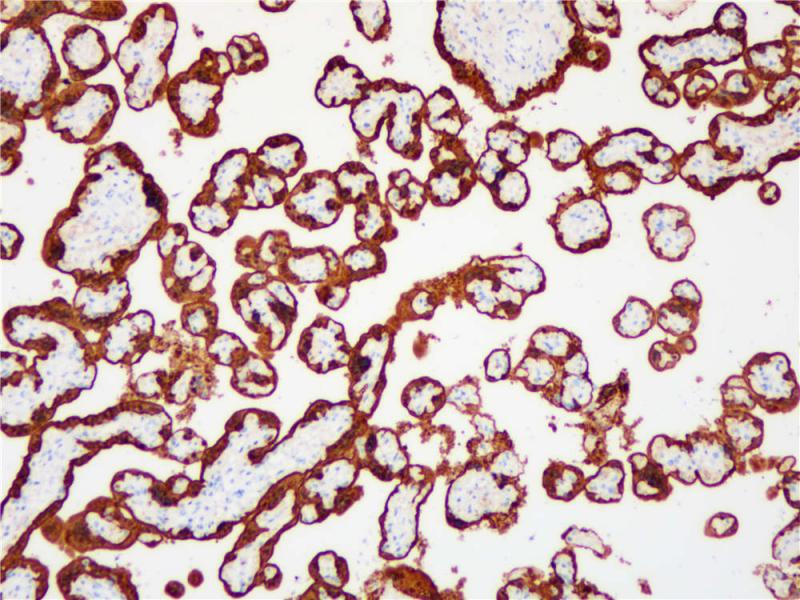

S100P 重组兔单克隆抗体

阳性对照

胎盘

亚细胞定位

细胞质/细胞核